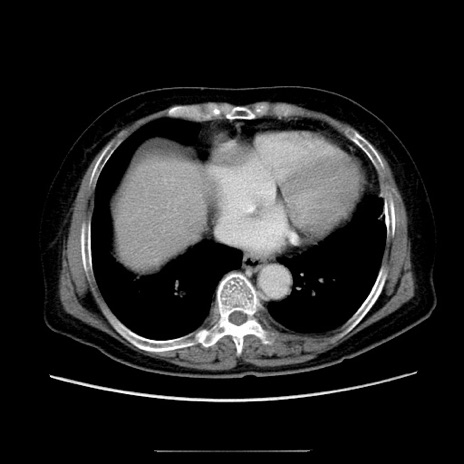

症例5(横断像)

【症例】70歳代女性

【主訴】お腹が張る

【現病歴】1週間くらい前から腹部膨満の自覚あり。昨日夜から増悪したため、本日救急外来受診。

【身体所見】意識清明、BT 36.5℃、BP 165/106mmHg、HR 80bpm、SpO2 98%、腹部:膨満、軟、自発痛・圧痛なし、触診にて不快感あり、腸蠕動音:減弱

【データ】WBC 12600、CRP 1.04